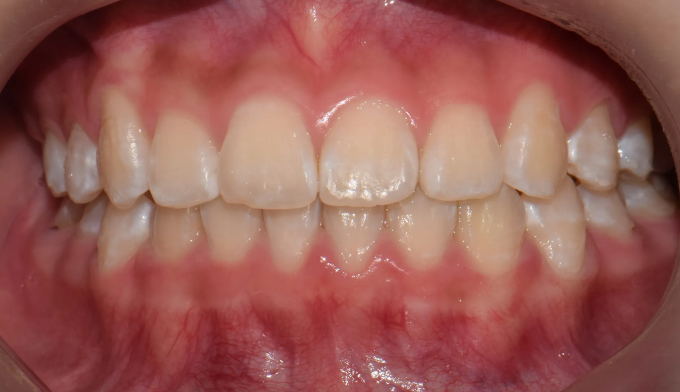

초등학생때 1차교정을 통해 앞니만 배열하였다고 했습니다.

진단해보니 송곳니가 나올 공간이 부족하여 2차교정을 진행하였습니다.

그래도 1차교정을 통해 공간을 어느정도 확보해 놓은것이 2차교정을 더 수월하게 해줍니다.

남아있는 공간을 최대한 활용하여 발치없이 치아를 배열해줍니다.

교정기간은 14개월 소요되었습니다.